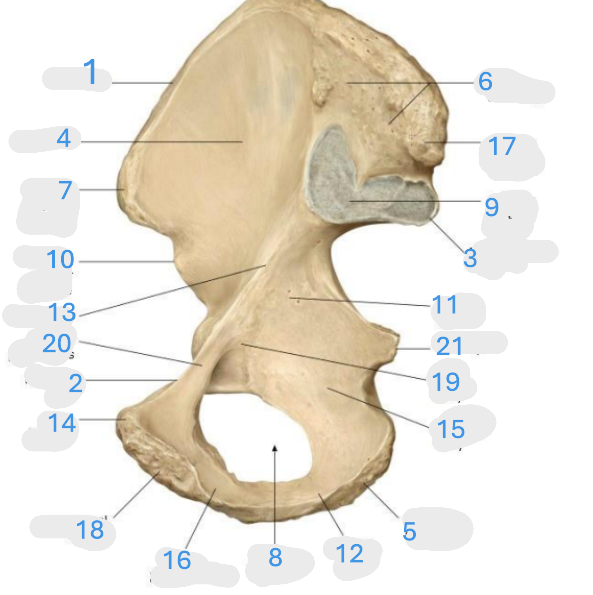

Where is the iliac crest

1

Where is the pubis body

2

Where is the ischium body

3

Where is the obturator foramen

4

Where is iliac wing

5

Where is the ilium body

6

Where is the ischial tuberosity

7

Where is the acetabulum

8

ischial ramus

9

Where is the superior pubic ramus

10

Where is the ischial spine

11

Where is the inferior pubic ramus

12